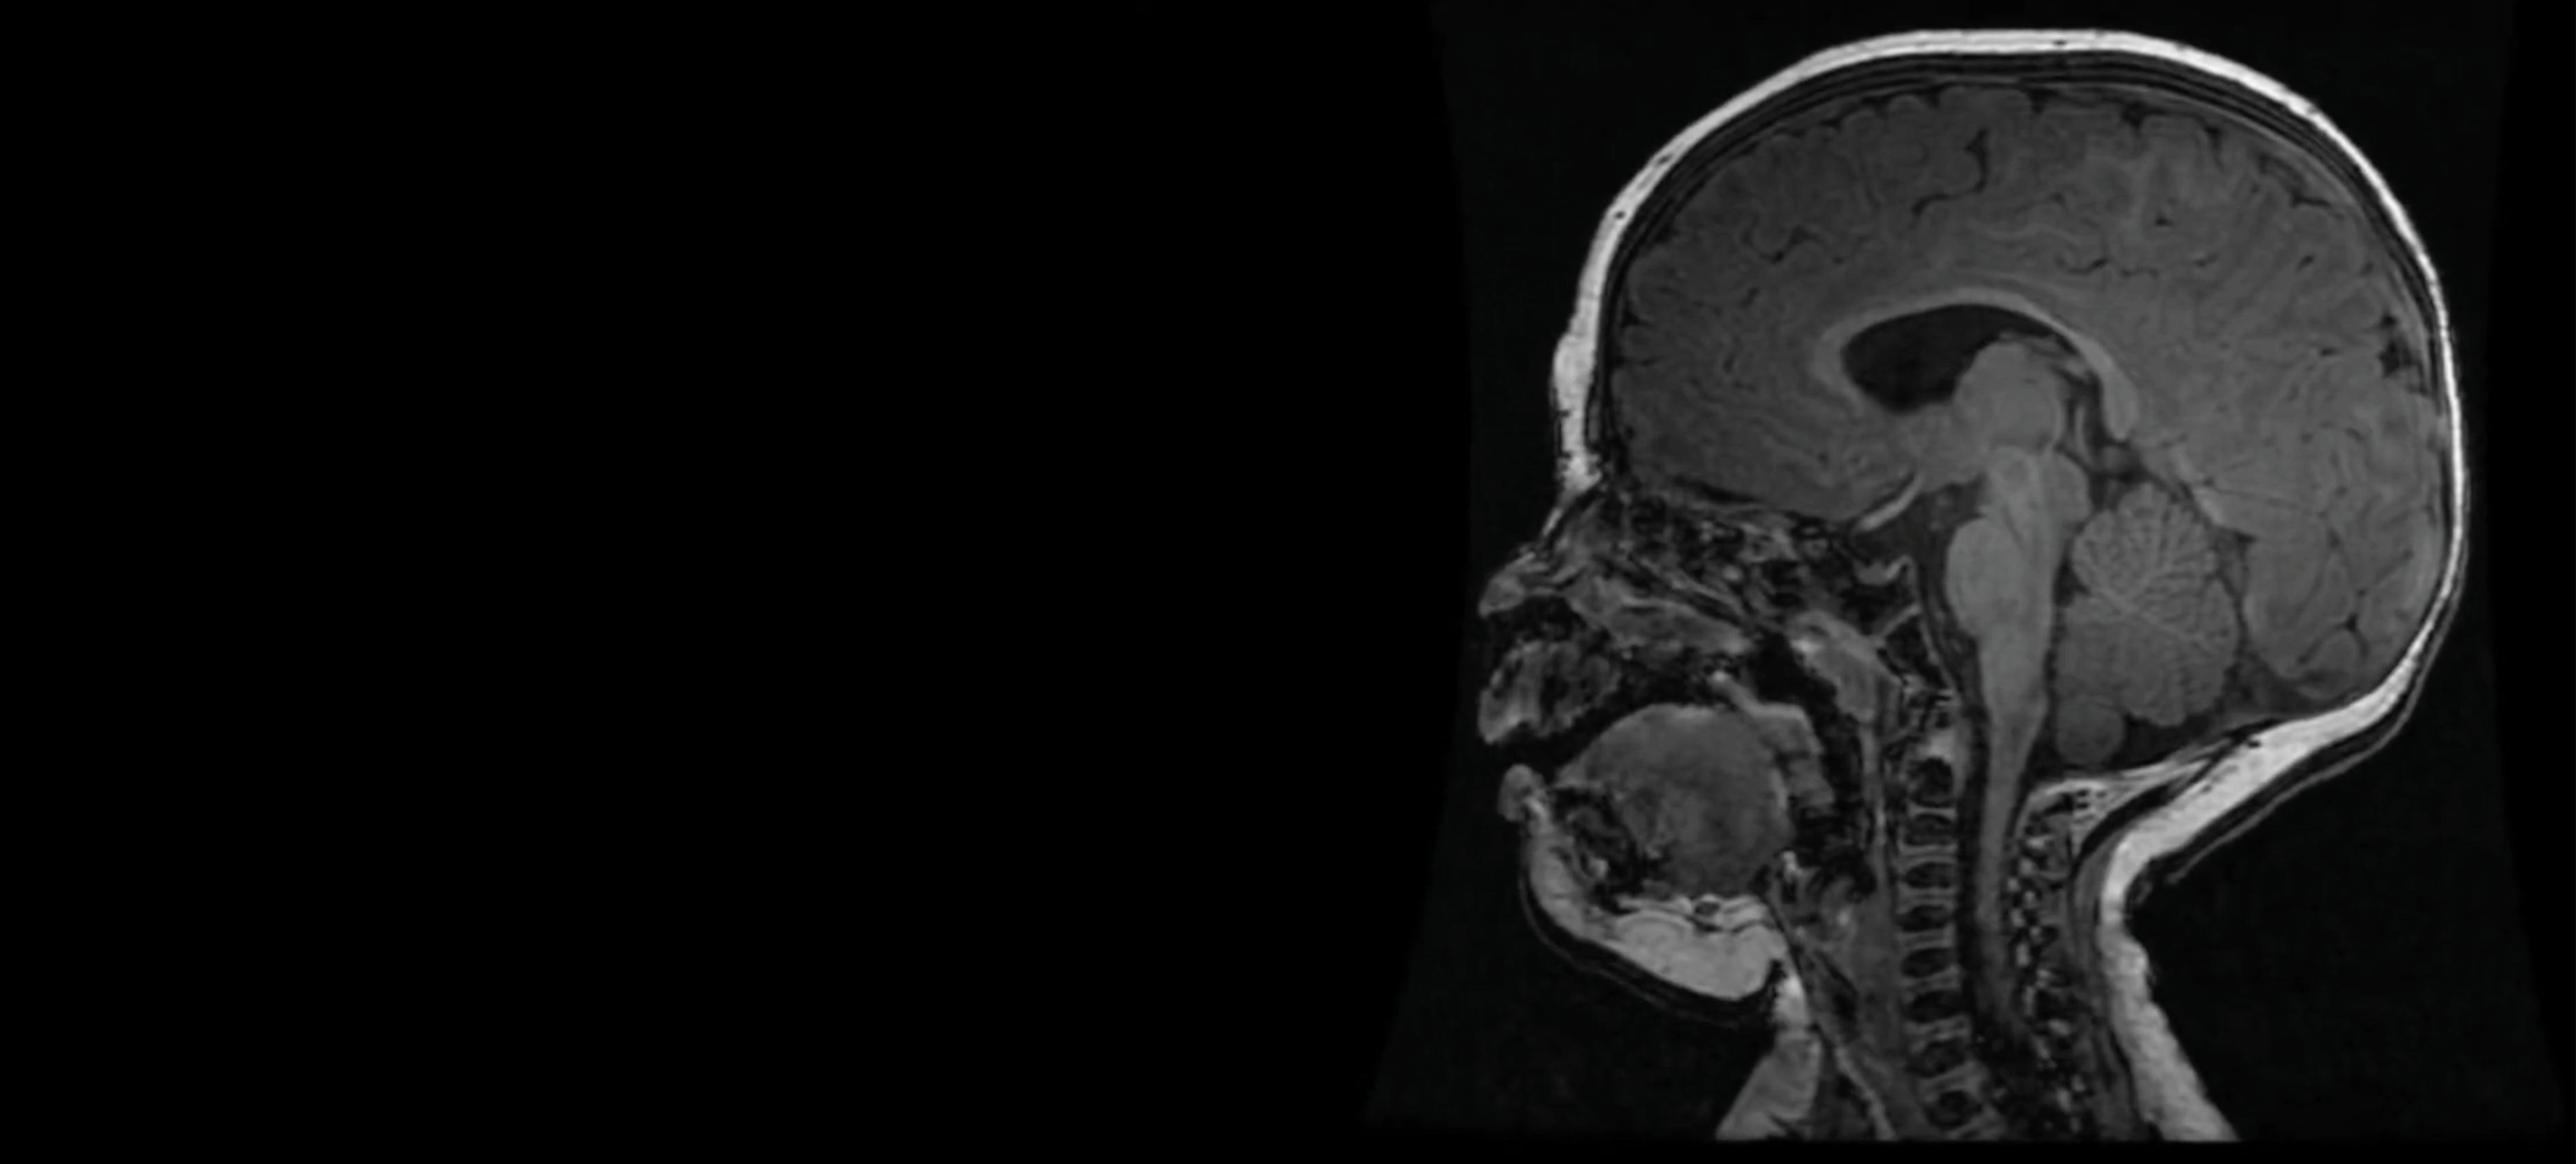

BAMRI Study

The Birth Asphyxia MRI (BAMRI) study implements innovative imaging techniques to assess infants who have encephalopathy in the neonatal period.  The study also evaluates the children as they mature to determine the long term effects of neonatal encephalopathy on brain development and neurodevelopmental performance.

The Birth Asphyxia MRI (BAMRI) project has been ongoing since 1993.  The goal was to see how sensitive MRI was in assessing brain injury of babies who had encephalopathy (abnormal neurological exam, seizures, abnormal blood gases) in the neonatal period.  We saw that brain injury occurred in certain patterns and were able to conclude that those patterns were associated with specific types of injury.  Some types of injuries resulted in damage to areas with high energy demands (brain stem, thalamus, sensorimotor pathways), while others resulted in damage to regions that got less blood flow when blood pressure went down or the heart didn’t contract forcefully.  Some babies had damage to the entire brain, presumably due to a long period with essentially no flow to the brain.  Still others, had very localized areas of injury, which we call a “stroke” or an infarct.  By looking at these patterns of injury and correlating them with outcomes when the babies came back for follow-up neurodevelopmental examinations, our team was able to predict reasonably well what outcome would be based upon the initial MRI.

As time passed, we got additional tools to use on the MRI and more powerful MRIs; these allowed us to do new and better examinations of the babies’ brains.  Proton MR spectroscopy (MRS) allowed us to look at effects of the injury on specific chemicals in the brain.  Diffusion weighted MR imaging (DWI), which looks at water motion in the brain, could show smaller areas of injury at earlier times and could be quantified to see how bad the injury was in different locations.  Even more important, MRS and DWI showed that the injury in the brain rapidly changed over the first few days; it got much worse between day 1 and day 4.  This finding was very important, because it taught us that early intervention might reduce the severity of brain injury.  This discovery led to the trial of therapeutic hypothermia (TH, also called “brain cooling”).  Recent studies have shown that brain cooling significantly reduces brain injury in some newborns, particularly those with injury to the areas with high energy demands when the injury is not very severe.  We think that the babies who do not respond well to TH have a different kind of injury, which has progressed beyond the stage where TH is effective.  Different therapies are now being formulated and will be used in upcoming trials to see if they are effective.

Overall, the prognosis for newborn babies with encephalopathy has improved greatly over the past 20 years, and the results of BAMRI have contributed significantly to that improvement!